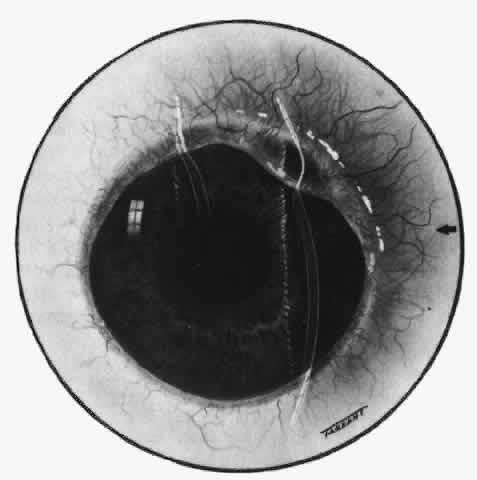

episcleritis and nodular episcleritis. ETIOLOGY Thirty percent of patients with episcleritis had some associated general conditions,6–8 but the rest defied all attempts to discover an etiology. Although some patients had a strong family history of atopy, results of patch and prick testing were uniformly negative. Of those in whom an etiology was found, only 5% showed any association with collagen disease, 7% had an association with herpes zoster, and 3% each had an association with gout or syphilis; the rest had associated conditions such as erythema nodosum, Schönlein-Henoch purpura, erythema multiforme, contact with industrial solvents, or penicillin sensitivity, indicating an immune basis for the condition. PATHOLOGY Microscopic and electron microscopic studies of biopsy specimens from patients with simple and nodular episcleritis have been totally noncontributory in the attempt to discover the etiology of this condition. The inflamed area is packed with lymphocytes and a few other inflammatory cells, but there are no mast cells, plasma cells, or eosinophils. CLINICAL MANIFESTATIONS The onset is usually acute; the eye may become red and painful in as short a time as half an hour. The patient's main complaint is redness of the eye, which is often sectorial and may be accompanied by a feeling of hotness, pricking, and mild discomfort. There is no discharge, although the eye waters occasionally. Pain may be absent, but the discomfort may be so severe that patients cannot pursue their normal occupation. The pain is localized to the eye, rarely radiating to the forehead and never producing the severe boring pain that is so commonly described in scleritis. In a severe attack the lids may become swollen, but this is a rare occurrence. If photophobia is present, an accompanying corneal condition should be suspected. Simple and nodular episcleritis differ in their clinical courses, but in both the edema and infiltration are entirely within the episcleral tissues. The sclera is not involved. The maximum congestion is in the superficial episcleral network, with some slight congestion of the conjunctival vessels and deep episcleral vessels (Fig. 10). The intraocular structures are not involved in either variety, nor is the visual acuity affected. Anterior segment fluorescein angiography reveals a normal vascular pattern but a very rapid flow rate, with the whole transit of the dye being completed within 2 or 3 seconds (Figs. 11 and 12).

The redness of simple episcleritis may be intense, varying from a fiery-red or a brick-red discoloration to a mild red flush, but it does not have the bluish tinge that is seen in scleritis. The distribution is usually sectorial but can involve the whole anterior segment of the globe. The episcleral vessels are engorged but retain their normal radial position and architecture (Figs. 13 and 14; Color Plate 1A). In simple episcleritis, there is a diffuse edema of the episcleral tissues. These tissues are sometimes infiltrated with gray deposits that appear yellow in red-free light. Surprisingly, the eye is rarely tender to the touch.